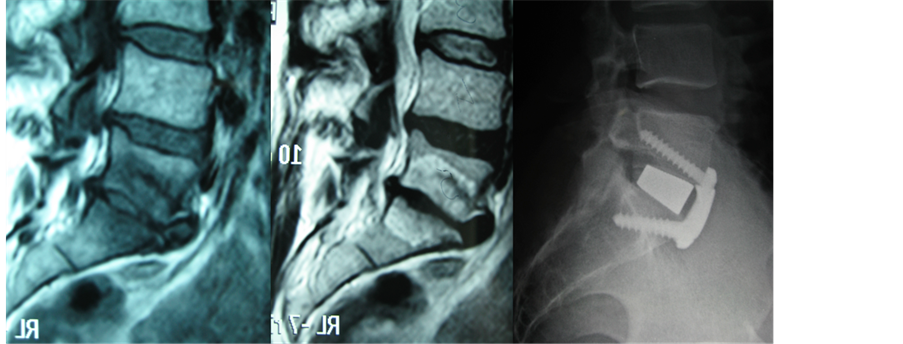

Figure 7. Preoperative sagittal lumbar MRI (T1 and T2 sequences) showing a L5-S1 discopathy (Pfirrmann 5) and postoperative X-ray (lateral view) of a L5-S1 ALIF. The patient has been treated with a tantallum cage and a three-screw anterior plate. This construct has the same stability than an anterior cage with four pedicle screws. It is clearly evaluable how the segmental lordosis have been properly increased after surgery.

surgical field wide open. Under endoscopic view and magnification, two horizontal cuts are performed with a scalpel on the anterior longitudinal ligament, corresponding to the upper and lower limits of the disc. A vertical incision is then performed on the midline, and the anterior ligament is detached from the midline laterally. This procedure results in two flaps that are preserved to be sutured together after the cage implant. The disc is then removed and the endplates prepared scrapping off the cartilaginous layer (Figure 4). Increasing sizes templates are then implanted in the intervertebral space, in order to find the proper fit (Figure 5). Finally, the definitive cage is implanted and fixed with an anterior plate with screws (we usually implant a three-screw plate for L5-S1 space, and a four-screw plate for the L4-5 disc) in order to increase primary stability (Figure 6). It has been demonstrated that a cage with an anterior plate has the same stiffness than a cage with posterior fixation (four pedicle screws) [3] (Figure 7). The whole procedure is performed through a 5 cm incision with the use of an endoscopic camera. This allows the best view on a HD monitor at a higher magnification for all the surgical steps, allowing a lesser invasivity and a better accuracy.